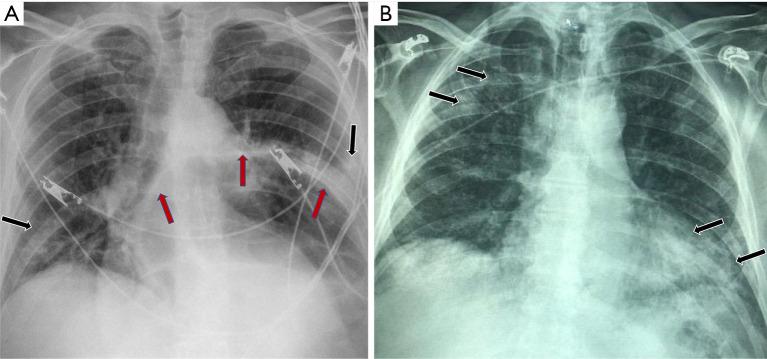

Radiological studies have an important role in the diagnosis and follow up of many infectious diseases. With current pandemic of Coronavirus disease 2019 (COVID-19) though the molecular analysis with reverse transcriptase polymerase chain reaction (RT-PCR) remains the cornerstone of diagnosis, the critical role of chest imaging including CT scan and baseline X-ray became apparent early in the course due to concern for less than optimal sensitivity of PCR testing. Delay in molecular diagnosis due to a shortage of testing kits and laboratory personnel also makes imaging an important modality in early diagnosis for appropriate triage and isolation decisions. CT scan technology is widely available in developed parts of the world but in developing countries, CT scanner is not widely available especially in rural settings. CT imaging usually requires patient movement to the radiology department and the scanner is not easy to disinfect. Point of care ultrasound (POCUS) has been used for many years in the assessment of critically ill patients in emergency departments and intensive care units. It is rapidly gaining popularity across many specialties and part of many general medicine training programs across the United States. It can be learned rapidly and with experienced hands, POCUS can help identify disease patterns in the lung parenchyma, and during the current pandemic has been gaining special attention. In this article, we review the most prominent imaging findings on chest X-ray and CT scan in patients with COVID-19. We also focus on the background and evolution of POCUS with studies showing the promising role of this diagnostic modality in COVID-19 infection. In addition, we describe step by step guidance on the use and disinfection of the portable ultrasound machine.

放射学研究在许多传染病的诊断和随访中发挥着重要作用。在当前的2019冠状病毒病(COVID-19)大流行中,尽管逆转录聚合酶链反应(RT-PCR)的分子分析仍然是诊断的基石,但由于担心PCR检测的敏感性欠佳,胸部成像(包括CT扫描和基线X线检查)的关键作用在病程早期就变得明显。由于检测试剂盒和实验室人员短缺导致分子诊断延迟,这也使得成像成为早期诊断中进行适当分诊和隔离决策的重要手段。CT扫描技术在世界发达地区广泛可用,但在发展中国家,尤其是在农村地区,CT扫描仪并不普及。CT成像通常需要患者前往放射科,而且扫描仪不易消毒。即时超声检查(POCUS)在急诊科和重症监护病房对危重症患者的评估中已经使用多年。它在许多专业领域迅速普及,并且是美国许多普通医学培训项目的一部分。它可以快速掌握,并且由经验丰富的人员操作时,POCUS有助于识别肺实质中的疾病模式,在当前大流行期间受到了特别关注。在本文中,我们回顾了COVID-19患者胸部X线和CT扫描最突出的影像学表现。我们还重点介绍了POCUS的背景和发展,各项研究表明这种诊断方式在COVID-19感染中具有重要作用。此外,我们还描述了便携式超声机器使用和消毒的逐步指导。